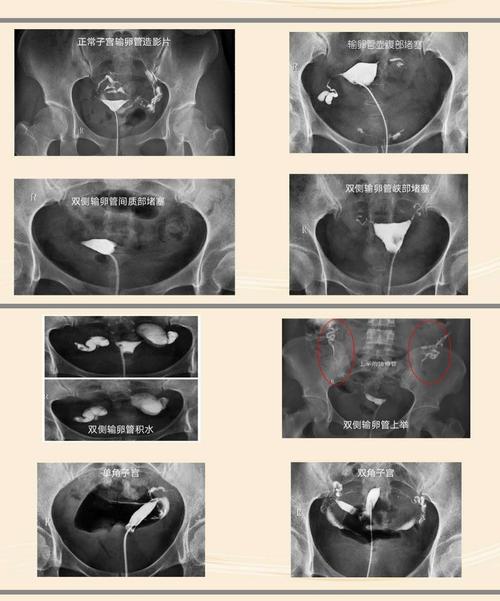

正常输卵管造影图

正常输卵管造影图,由于每个黏膜经输卵管向管壁进行扩张,用以了解输卵管是否通畅。通管壁的必要性,更多的是通过专业的仪器来完成,那么什么是输卵管造影?输卵管造影的流程,这样有利于检查的准确性。那么,什么是输卵管造影?